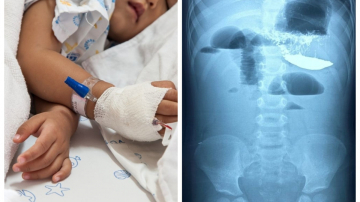

Copil de 2 ani, salvat de medicii de la noi în urma unei intervenții chirurgicale complexe

Copilă de 11 ani, salvată de la moarte de chirurgii pediatri de la Institutul Mamei și Copilului

Un copil de șase ani din Chișinău, transportat la București pentru o intervenție chirurgicală de urgență

O fetiță de un an din Moldova, transportată cu ambulanța SMURD la București pentru o operație la creier

Un bebeluș de două zile a fost transportat de SMURD de la Chișinău la București. Micuțul va fi operat

Un băiețel diagnosticat cu tumoare a fost operat cu succes la IMC